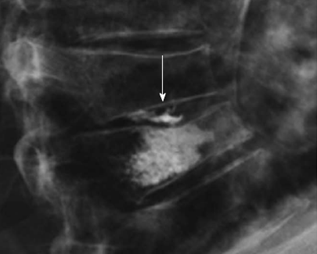

Radiological Society of North America. Osteoporosis. Available at <http://www.radiologyinfo.org/en/photocat/gallery3.cfm?image=xray-osteoporosis-vertebroplasty.jpg&pg=osteoporosis > Accessed 13 December 2014.